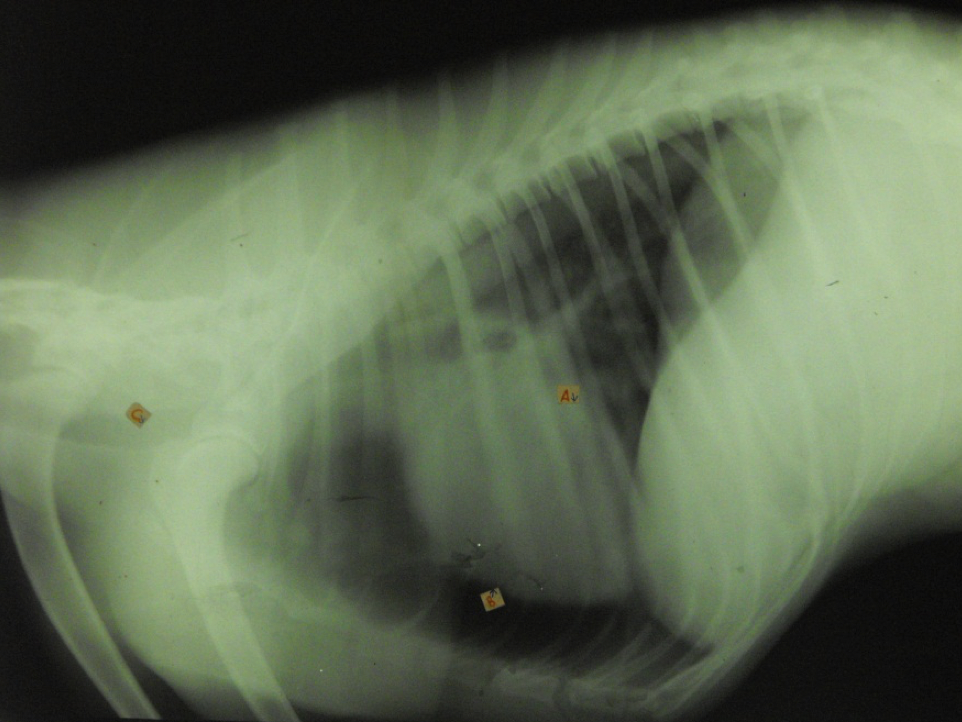

identity the structures on the thorax radiograph left lateral view

heart

identify the right cranial pulmonary vein

identify the pulmonary arteries

identify the right cranial lung lobe

identify the right cranial bronchus

identify the right accessory lobe of the lung

identify the right crus of the diaphragm

identify the left crus of the diaphragm

identify the dome of the diaphgram

identify the left cranial lung lobe